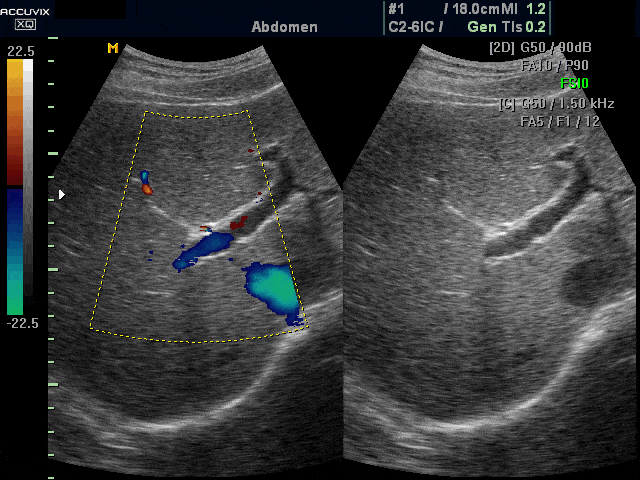

[RU] Ultrasound image №395: Liver blood flow (dual dynamic display) in color doppler mode.

Echogramm was received by ultrasound scanner Accuvix-XQ (out of production).